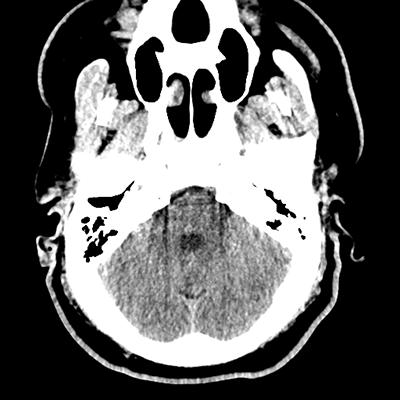

NCHCT

NCHCT 1/16 1/16